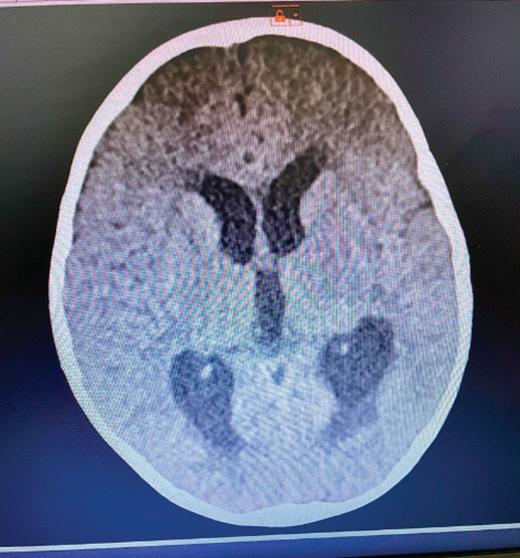

Патогенезата на заболяването, представена съвсем накратко, е следната: Mycobacterium tuberculosis→по въздушно-капков път достига до алвеоларните макрофаги, развива се бактериемия→туберкул→субарахноидално пространство→менингит. Ако от менингите бактерият достигне и до мозъчния паренхим→туберкуломи

абсцеси→ексудат от абсцесите при отварянето им инфилтрира

кортикалните и менингеални кръвоносни съдове и води до мозъчно възпаление и инфаркт. Развива се характерен базален менингит, засягат се предимно III, VI и VII ЧМН и се развива обструктивна хидроцефалия→адхезия + облитериращ васкулит + енцефалит или миелит.

Етиологичната диагноза на туберкулозния менингоенцефалит по обективни причини е възможна в 6-10% от заболелите деца. Поради това диагнозата е комплексно обусловена. Епидемиологичната анамнеза, симптоматиката на базален менингит и характеристиката на ликворния синдром са патогномонични и поставят диагнозата. Абсолютно необходимо е диагностичния процес да продължи с туберкулинов тест на Манту, микробиологично изследване на ликвор (директна микроскопия, посявка на MGIT, PCR real time, BACTEK); SPOT TB; QFT in tube; Рентгеново изследване на белите дробове; КАТ, ЯМР на мозъка.

Беше осъществено Рьо на бели дробове: липсват рентгенови данни за патологични засенчвания в белодробния паренхим двустранно. К.д. синуси – свободни. Сърце и медиастинум – б.о. Контролна КАТ на главен мозък: екстремно разширени вентрикулни отдели на ликворната система. Намален

око

цистерни. Заключение: КТ данни за тежка вътрешна хидроцефалия